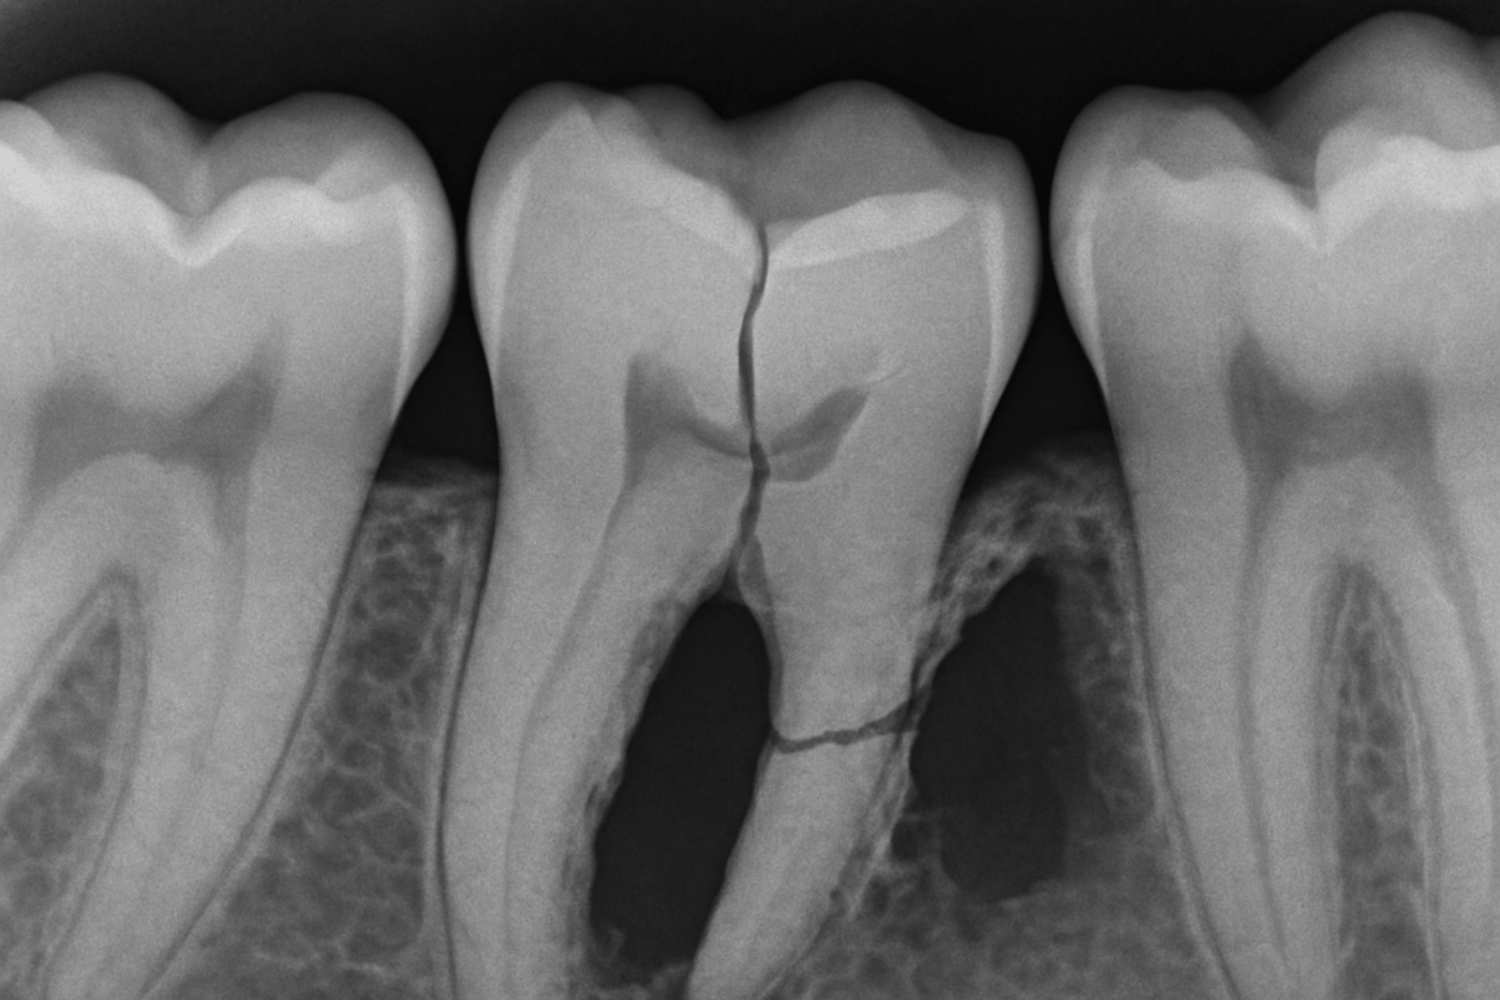

A broken tooth untreated doesn’t remain stable – it continues deteriorating in predictable stages. Understanding this process helps illustrate why prompt treatment is essential for preserving the tooth’s structure and avoiding more extensive dental work.

Initially the crack typically expands due to normal chewing forces and temperature changes. Each time you bite down or drink something hot or cold, the materials in the tooth expand and contract at different rates, causing the crack to propagate deeper into the tooth’s structure.

Then if decay does occur, decay can accelerate as bacteria colonize the crack and produce acids that further weaken the tooth. The bacteria convert sugars from your diet into lactic acid, which dissolves the mineralized tooth structure and creates larger cavities around the original break.

The structural integrity becomes so compromised that larger pieces may break off during normal eating. What started as a minor chip can progress to losing significant portions of the crown, requiring much more extensive restoration or extraction.

Root development may occur and reach below the gum line. At this point, the tooth’s root may be too damaged to support any type of restoration, making tooth extraction the only viable option.

Since tooth enamel cannot regenerate like other body tissues, any cracks or chips are permanent and progressive. Unlike a broken bone that can heal stronger than before, teeth have no mechanism for self-repair, making professional intervention the only way to halt deterioration.